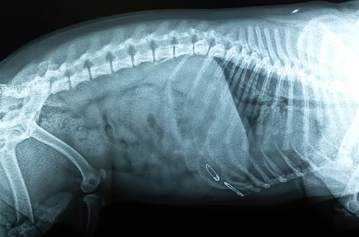

버튼 배터리는 삼키면 매우 위험하다. 같은 장소에 머무르면 점막이 부식되어 위나 장 등 내장에 구멍을 뚫어버리는 경우도. 반려견이 배터리를 삼켰다면 최대한 빨리 동물병원에 가서 엑스레이를 찍고 삼킨 배터리가 어디에 있는지 확인하고 꺼내는 조치가 필요하다.